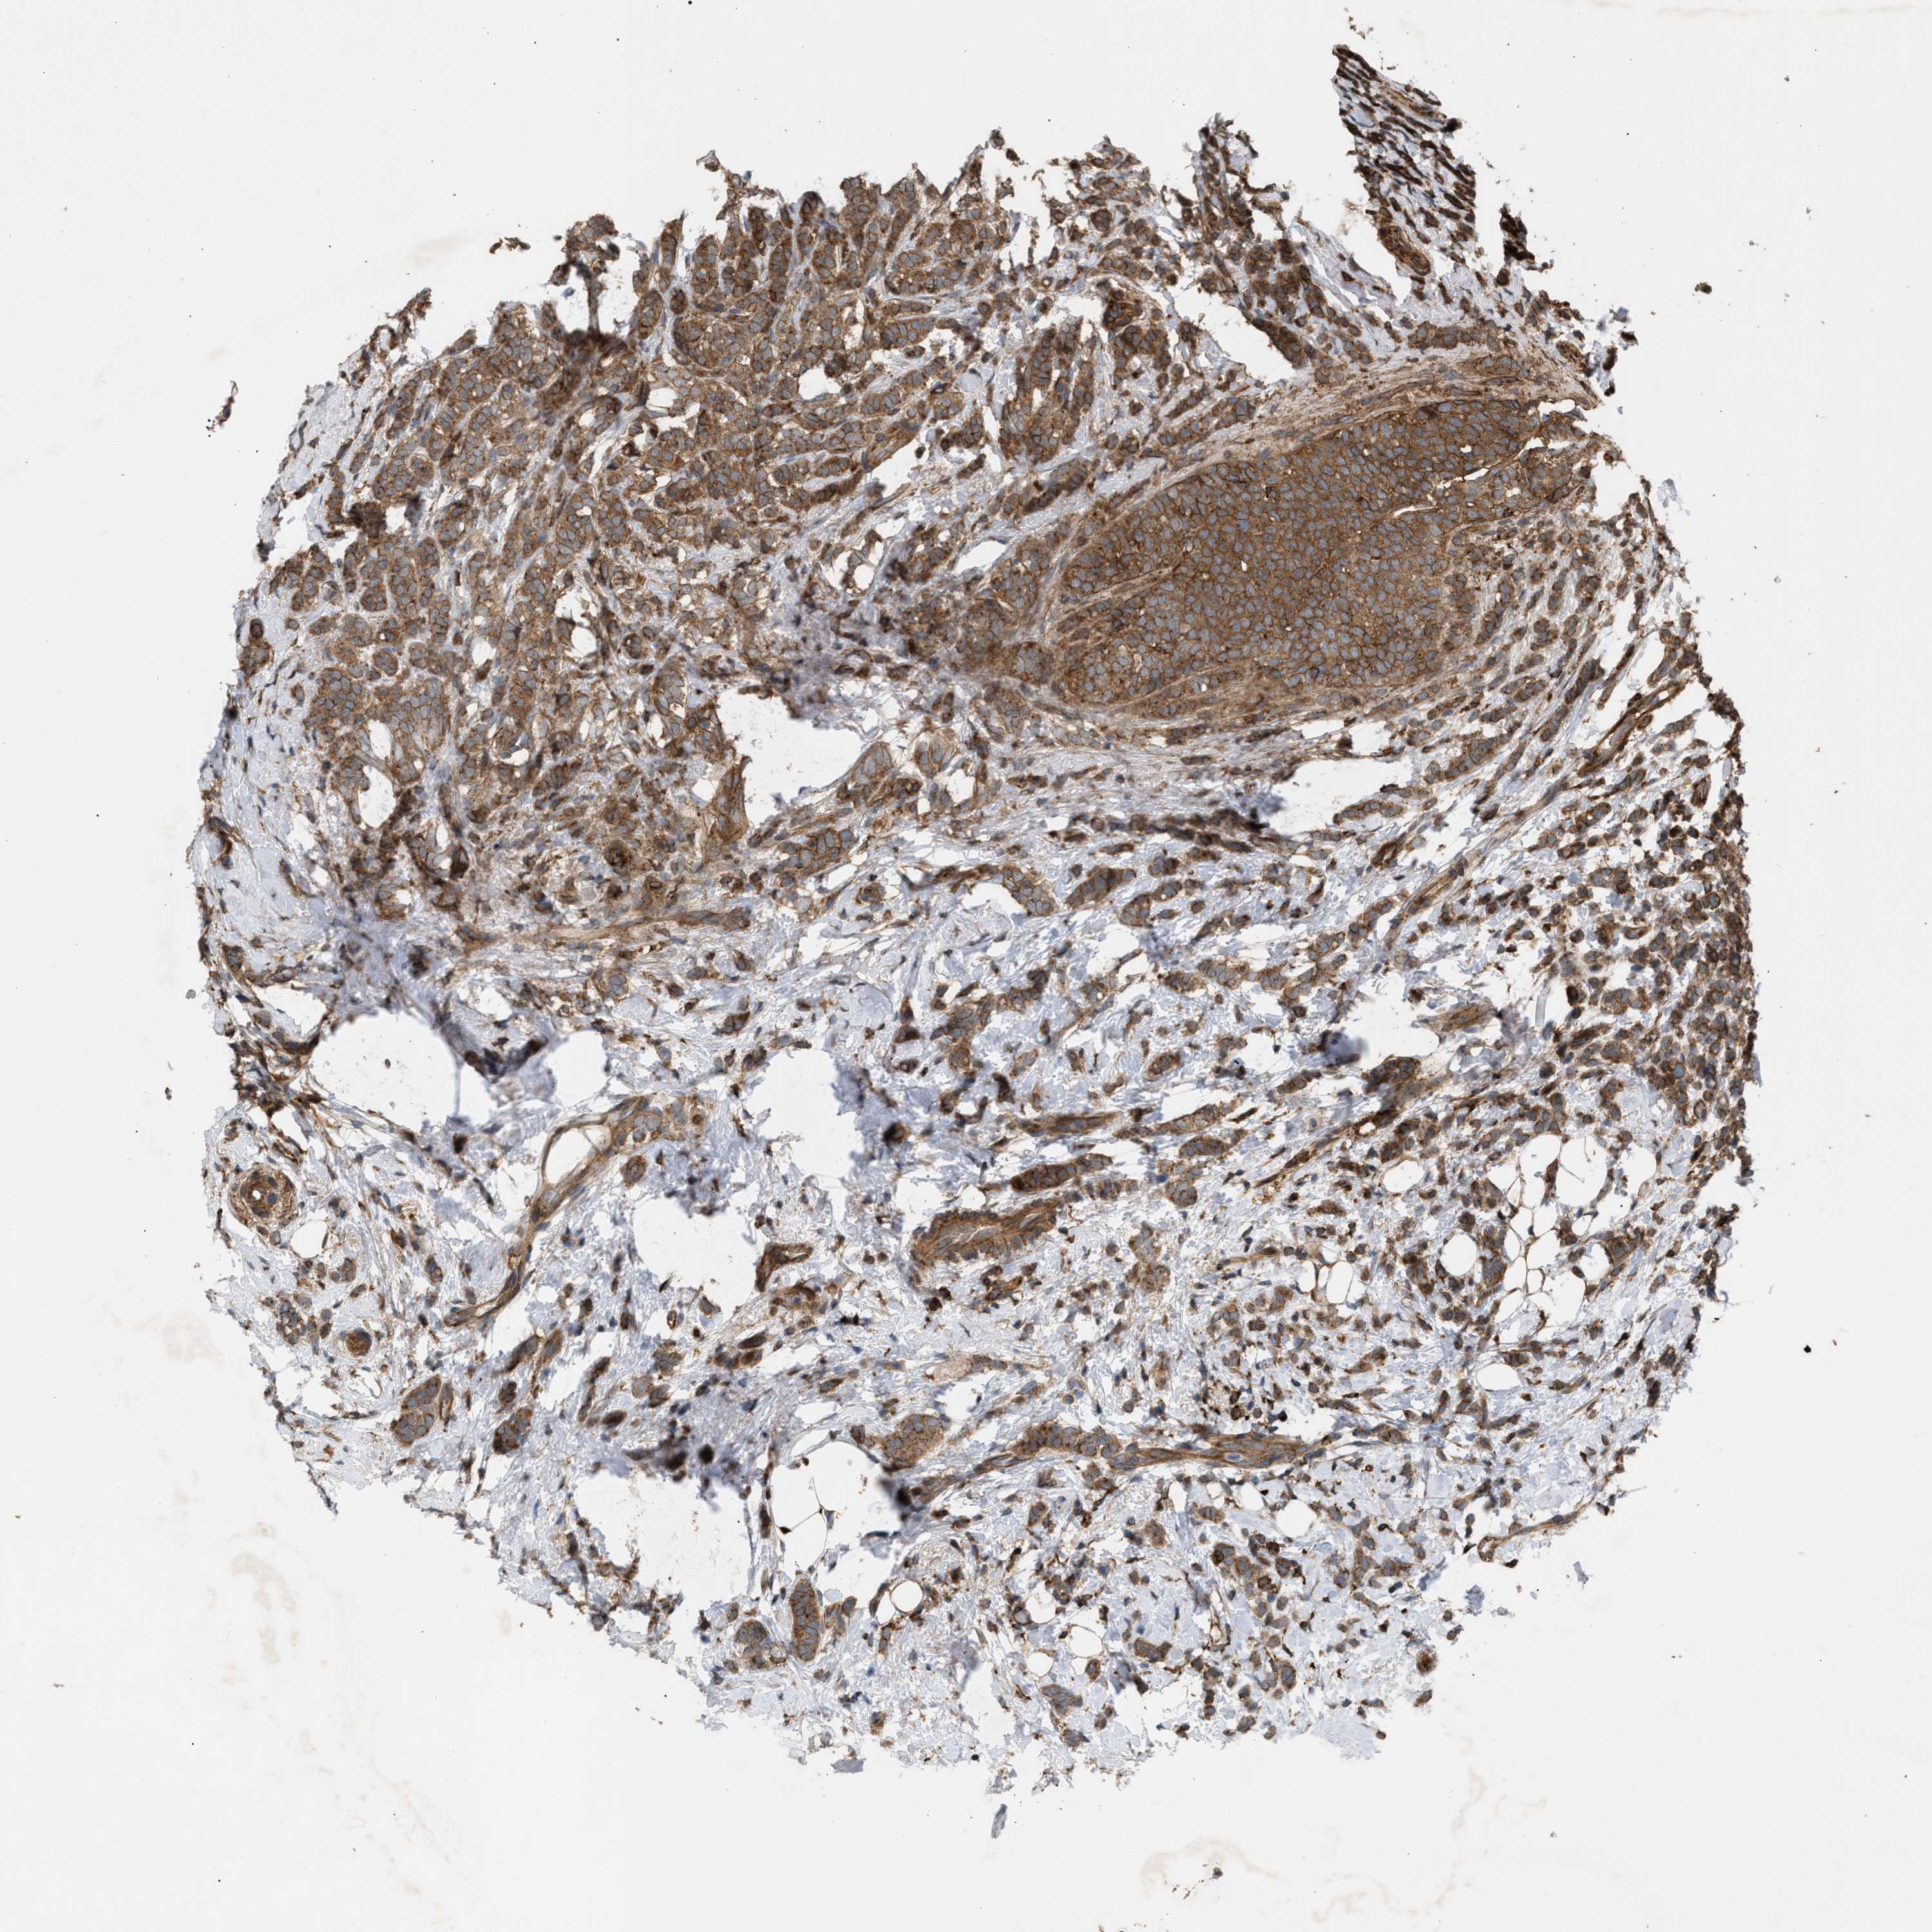

CANCER BREAST CANCER Show tissue menu

BRCA TCGA BRCA VALIDATION PROTEIN EXPRESSION